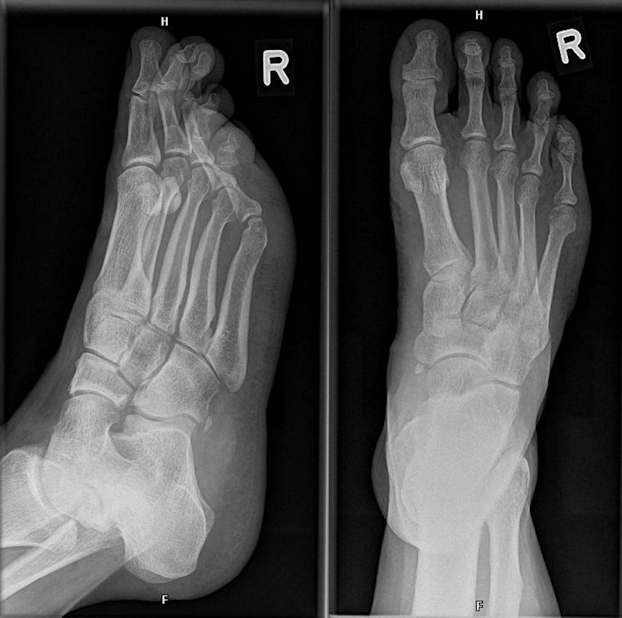

The foot with suspected fracture was imaged with conventional X-ray in two plains: axial and mediolateral (Figure 2 [Fig. 2]). However, no disruption of the bone continuity could be seen. Because of persistently pain a MRI scan was performed 10 days after trauma. There was no indication of a ligament rupture but a suspicion of a fracture of the right processus anterior calcanei. A CT scan was therefore conducted which revealed a calcaneus fracture line (Figure 3 [Fig. 3]).

Figure 2: Scan of the calcaneus with a discrete fracture without dislocation of the bone: Conventional X-ray taken at the initial examination